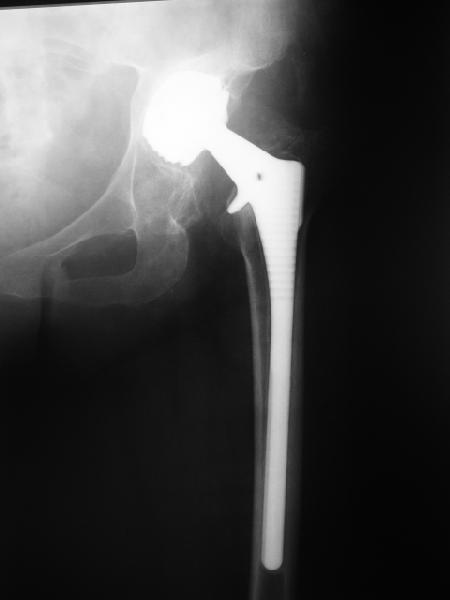

В наше отделение обратилась больная (родственница одного из сотрудников) 1948 г.р. В 2002 г. тотальное эндопротезирование тазобедренных суставов в Кургане.

Все было благополучно до 22 апреля этого года, когда при развороте на фиксированной стопе появилась резкая боль в правом тазобедренном суставе и верхней трети бедра. Конечность стала неопорной. Активные движения - резко болезненны. Пассивные - свободные, безболезненные. Местно - есть зона гиперемии в вертельной области. Пальпаторно - флуктуация (гематома?) по задне-наружной поверхности бедра. Температура субфебрильная. Больная сейчас на постельном режиме, двигаться, а тем более вставать отказывается из-за боли. Снимки прилагаются. Больная обращалась в клинику эндопротезирования Уральского НИИТО, ей было отказано даже в консультации.

24 апреля 2005 г. правый сустав фас (тут и болит)

24 апреля 2005 г. правый сустав профиль (тут и болит)

Хорошо бы взглянуть на снимок после операции.Я не знаком с этим идом протеза-но ацетаб. компонент напоминает Шустеровский. И ощущение что он как-то глубоко.

С выбором имплантата можно не согласиться, но скорее всего просто поставили то, что было в наличии. :( Вертлужный компонент установлен

слишком медиально. По представленным рентгенограммам нельзя исключить нарушение целостности дна вертлужной впадины. Даже если в данным момент нестабильности нет, то она обязательно возникнет и скорее всего, создаст

дополнительный дефицит костной ткани. Так что делать ревизию нужно, но только после исключения инфекции. Стандартные тесты - пункция сустава (в

Вашем случае и гематомы), СОЭ, СРБ. Антибиотики показаны только при подтверждении инфекции. В этом случае - удаление протеза, дебридмент, в/в антибиотики. В перспективе - можно рискнуть и протезировать повторно, но своим знакомым я бы этого не рекомендовал... :(

Простите-не заметил последнего приложения.Не вижу рентгенологических признаков loosening.Так что изотопы могли бы и помочь

На представленных Р-граммах явных признаков нестабильности эндопротеза нет. Чашка хоть и медиализирована, но стоит так же, как и 3 года назад и остеолиза нет. Есть остеолиз вокруг проксималного отдела ножки, но линия тонкая и не захватывает дистальный отдел. Судя по клинике, можно думать о травме (отрыв) ягодичных мышц в

зоне прикрепления к б/вертелу. Я бы рекомендовал пункцию этой зоны с эвакуацией гематомы и введением анестетика. Если после этого боль уменьшится или пройдет, то вы на правильном пути. Дальше - противовоспалительная терапия, покой и т.д.

2. Судя по рентгенограммам явной нестабильности тазового ибедренного компонентов не видно, но это не решает проблемы. Гематома? - пунктируйте - не инфекция ли? Посев пунктата нужен. 3. Не спешите - погодите по времени - возможно имеет место банальная травма в области искусственного сустава с гематомой - все пройдет. Ревизия только при убеждении в нестабильности компонентов сустава или при инфекции, что пока не манифестирует. Еще раз - не спешите, не горит. С уважением и с праздником. А Рыков Хабаровка.